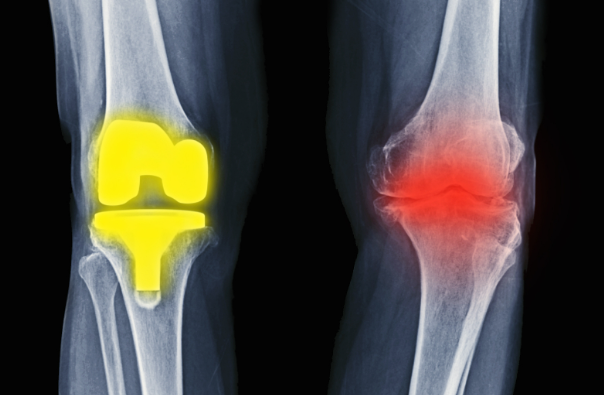

5、骨关节营养:

骨关节健康不良的主要表现为骨关节炎(osteoarthritis, OA)。骨关节炎是由多种因素引起关节软骨纤维化、皲裂、溃疡、脱失而导致的以关节疼痛为主要症状的退行性疾病。骨关节疾病常见病因是由于关节软骨受到过度或不正常的压力,导致软骨细胞和基质的异常代谢,从而引起软骨的退化和裂解。随着疾病的进展,软骨的降解最终超过了合成,导致进行性的软骨丢失和骨质象牙化。我国40岁以上人群原发性骨关节炎的总体患病率高达46.3%,中国症状性膝关节骨关节炎患病率的总体估计值为14.6%,腰椎骨关节炎患病率为25.03%。随着我国人口老龄化的加剧,OA的患病率逐渐上升。